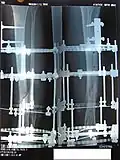

Процедура лечения открытого перелома большой и малой берцовой костей аппаратом Илизарова. Фотографии и рентгенограммы одного и того же пациента в течение курса лечения. Снимки 2 — 6 сделаны через четыре недели после перелома (две недели после наложения аппарата).

Рентгенограмма перелома и первоначальный внешний фиксатор, наложенный в течение 24 часов после поступления в больницу.

Рентгенограмма места перелома сразу после наложения аппарата Илизарова